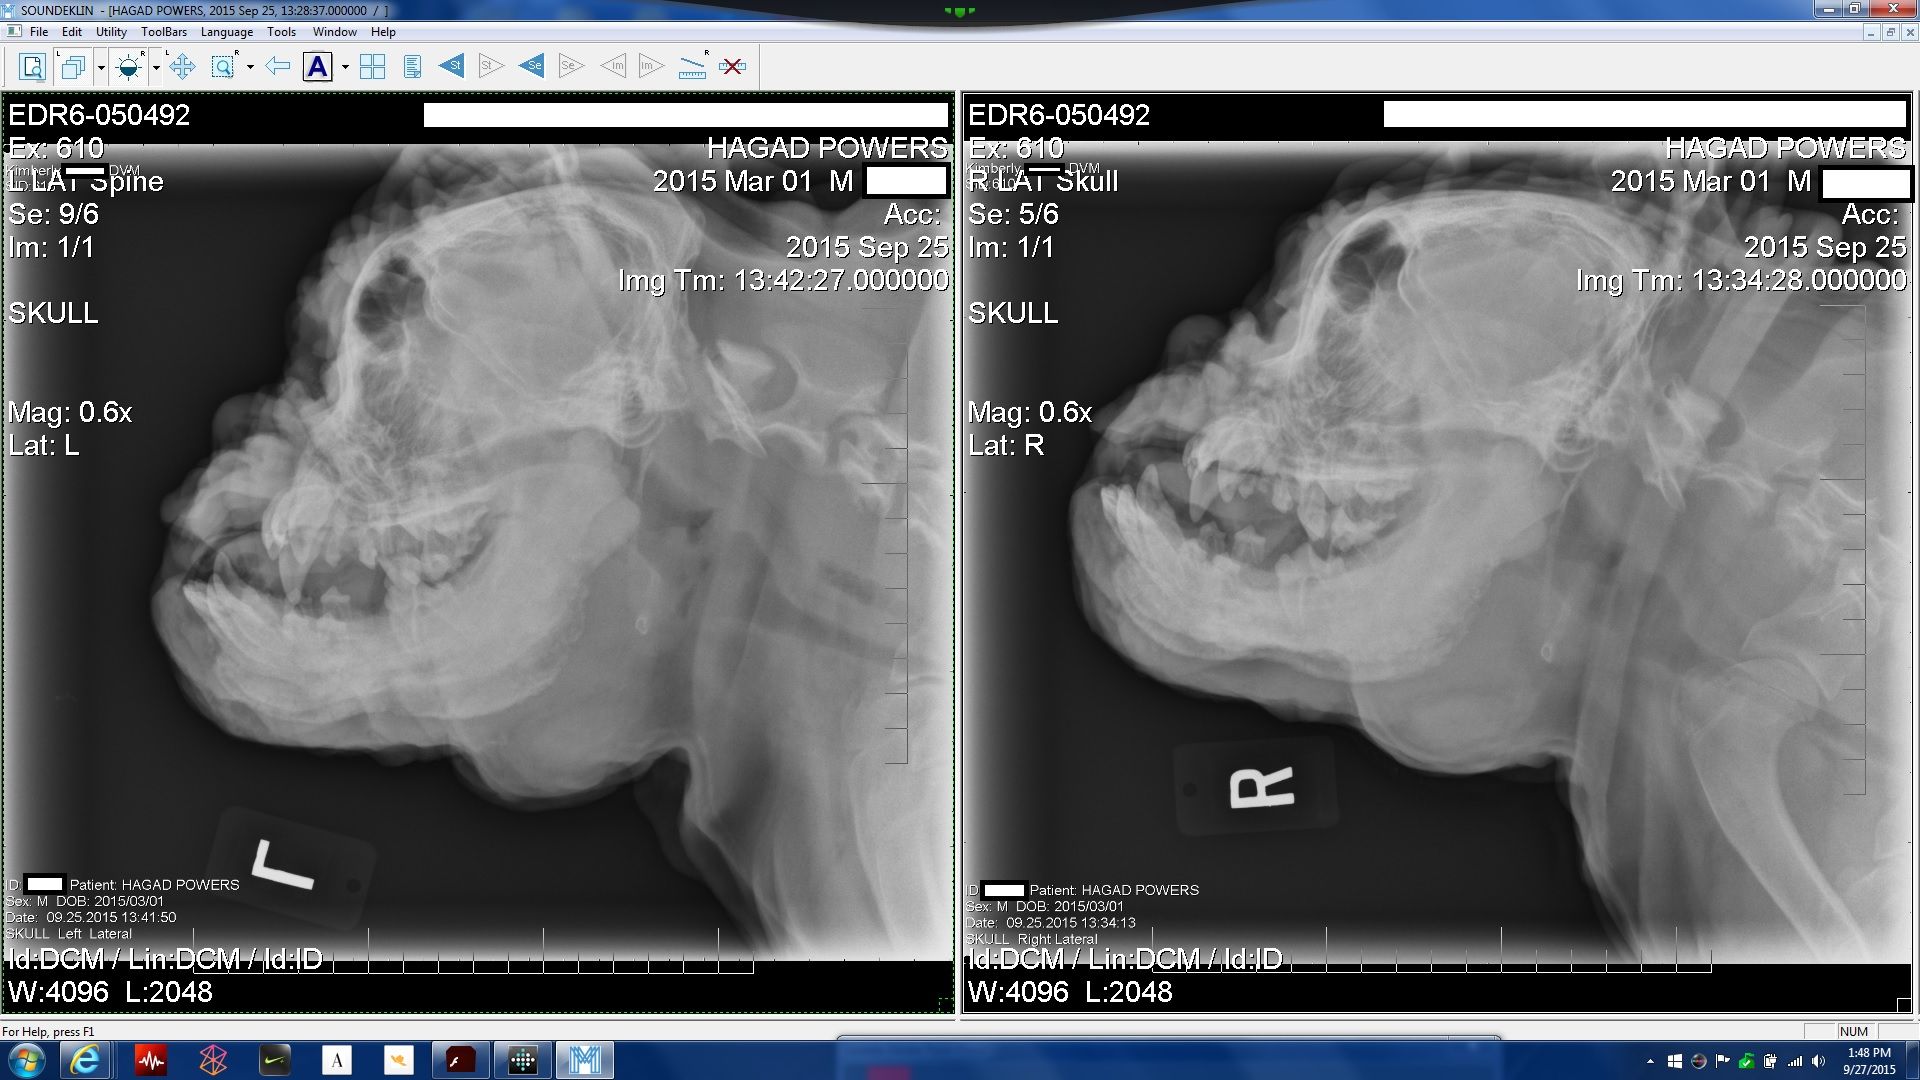

So sorry this is happening to and the little guy. Just read about mandibular osteopathy and hopefully you have a mild case here and the growing stops soon. Sending positive and healing thoughts your way.